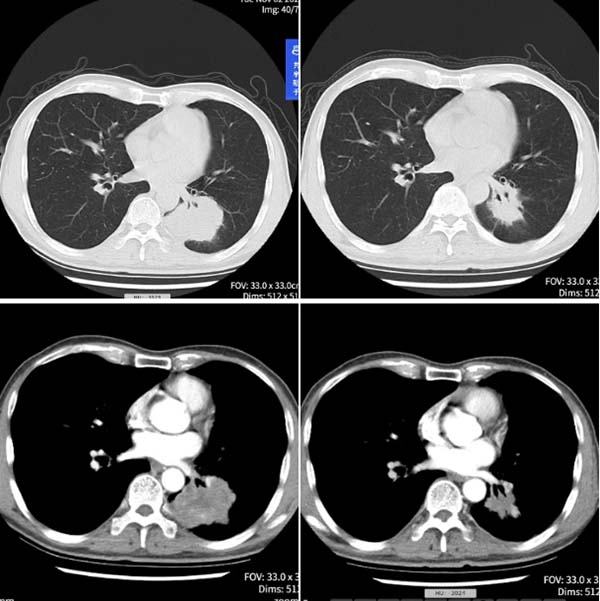

功夫不负有心人。经过两个周期治疗,陈老的肿瘤显著缩小,疗效评估达到“PR”(部分缓解),身体状况稳步改善。他在感谢信中深情写道:“是你们精神上的鼓励,让生命得到了延续……是你们用有力的双手托起生命的太阳!”

治疗前 ; 治疗2周期后

(2021-11-2) ; (2022-1-6)